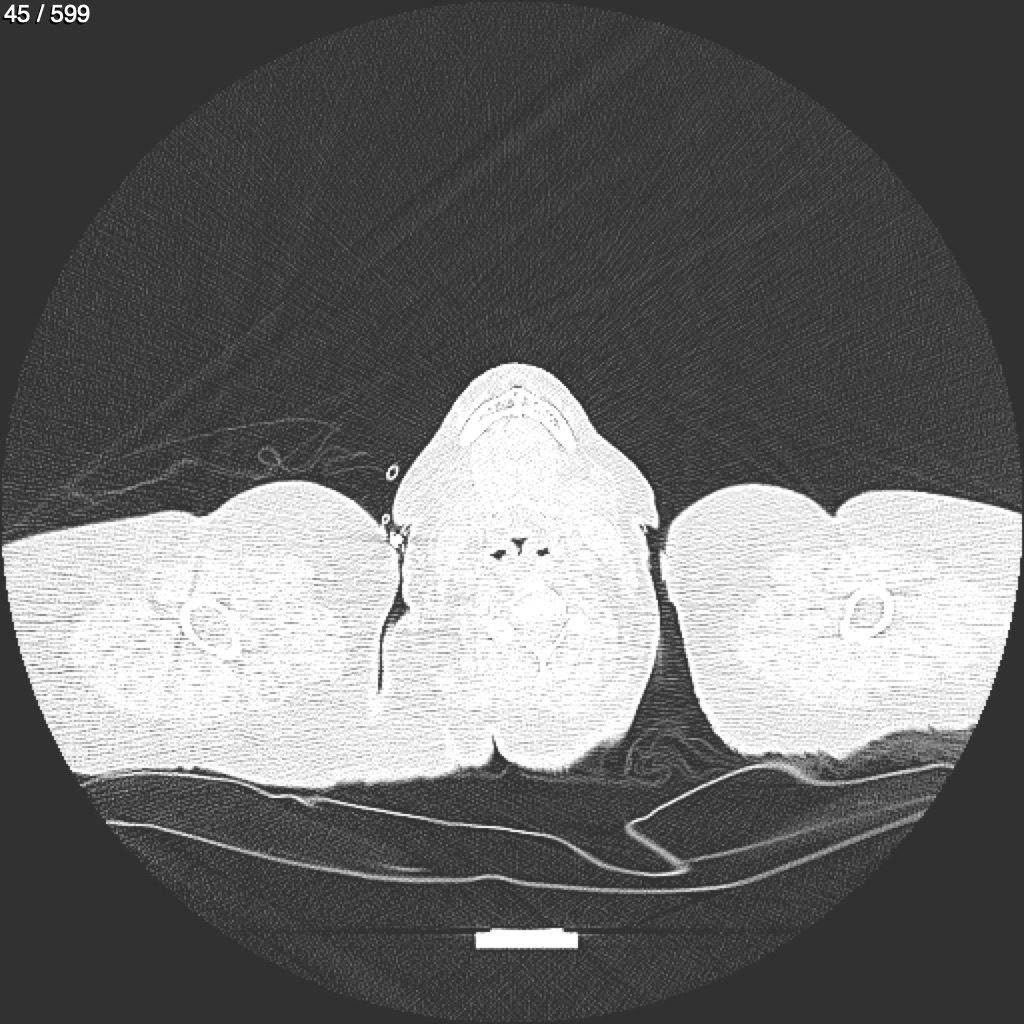

Home G​l​o​r​i​a​ ​G​l​a​d​y​s​ ​B​e​a​s​l​e​y​ ​-​ ​T​ó​r​a​x​ ​T​o​r​a​x​_​S​i​m​p​l​e​ ​(​A​d​u​l​t​o​)